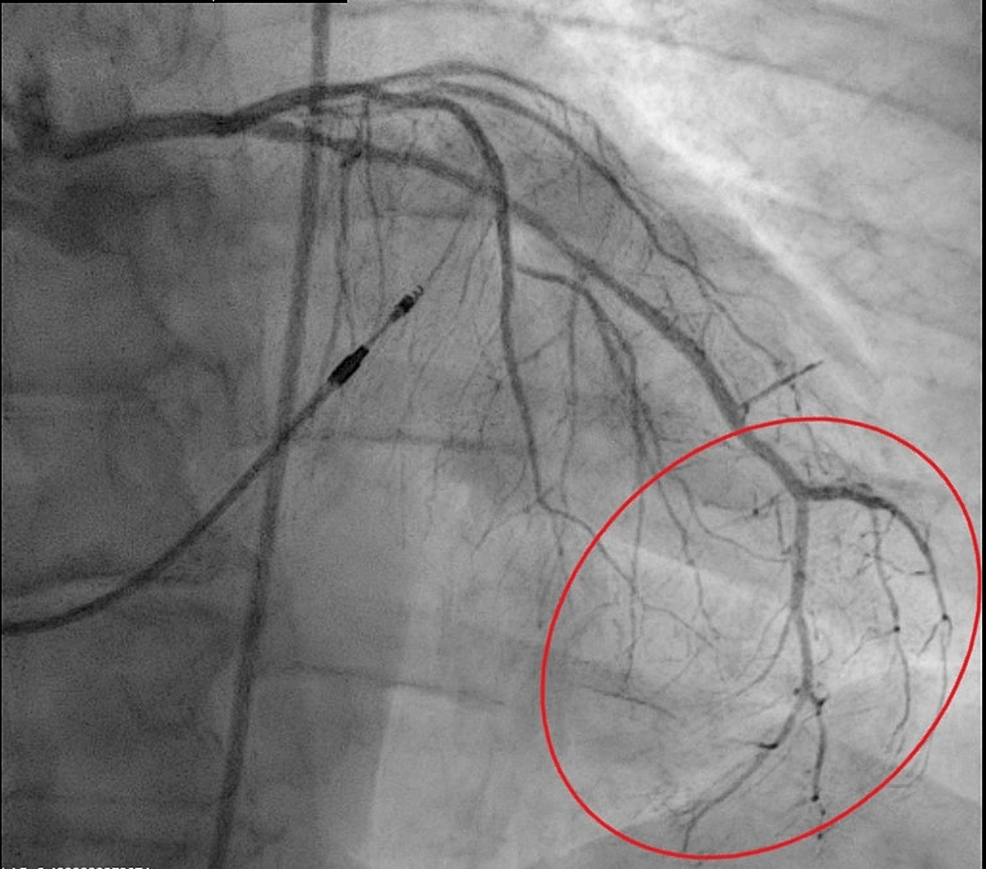

Angiographic image of right coronary artery demonstrati Openi

Web a large left circumflex artery displayed a mild luminal irregularity. Web coronary artery calcification is a collection of calcium in your heart’s two main arteries, also called your coronary arteries. Coronary thrombosis or embolism can result in minoca,. Web coronary microvascular dysfunction may contribute to minoca and requires further investigation. This happens after you've had plaque (fat and cholesterol). Web coronary artery disease (cad) is when one or more arteries in the heart are obstructed or narrowed by plaque deposits forming along artery walls. Web even mild narrowing (26% to 50%) of the left main coronary artery (66 patients) was generally accompanied by 51% to 75% or greater narrowing of at least one. Web luminal irregularities of coronary artery • concept id: Luminal irregularities of coronary artery (371873004) recent clinical studies. Web a coronary artery that’s severely narrowed by multiple plaques or one or two long plaques may not be salvageable through stenting or surgery.